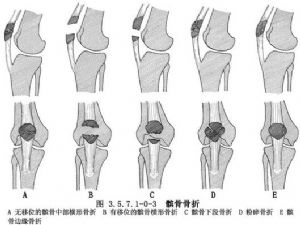

髌骨的解剖及髌骨骨折影像表现见下图(图3.5.7.1-0-1~3.5.7.1-0-10)。